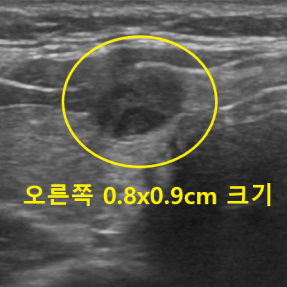

유방암 · 갑상선암 진단사례

Thyroid Clinic

정확한 검사와 해석으로 건강한 일상을 되돌려드립니다.